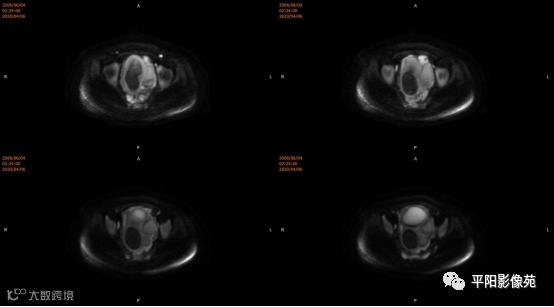

患者,女,13岁

主诉: 下腹部胀痛2+月,加重1天

现病史: 患者月经未来潮,2+月前无明显诱因感下腹部憋胀,间断胀痛,可忍耐,伴排便困难,自认为便秘引起腹胀,未在意。近1+月腹胀、胀痛次数增加,觉下腹部逐渐增大,小便正常。

您的诊断?

4.MRI检查 对软组织分辨率好,能够清晰区分子宫及阴道,对子宫内膜、结合带、肌层可清晰分辨;能明确子宫、宫颈、阴道结构异常的部位、范围、性质等。宫腔内经血潴留时,宫腔内见短T1长T2信号。